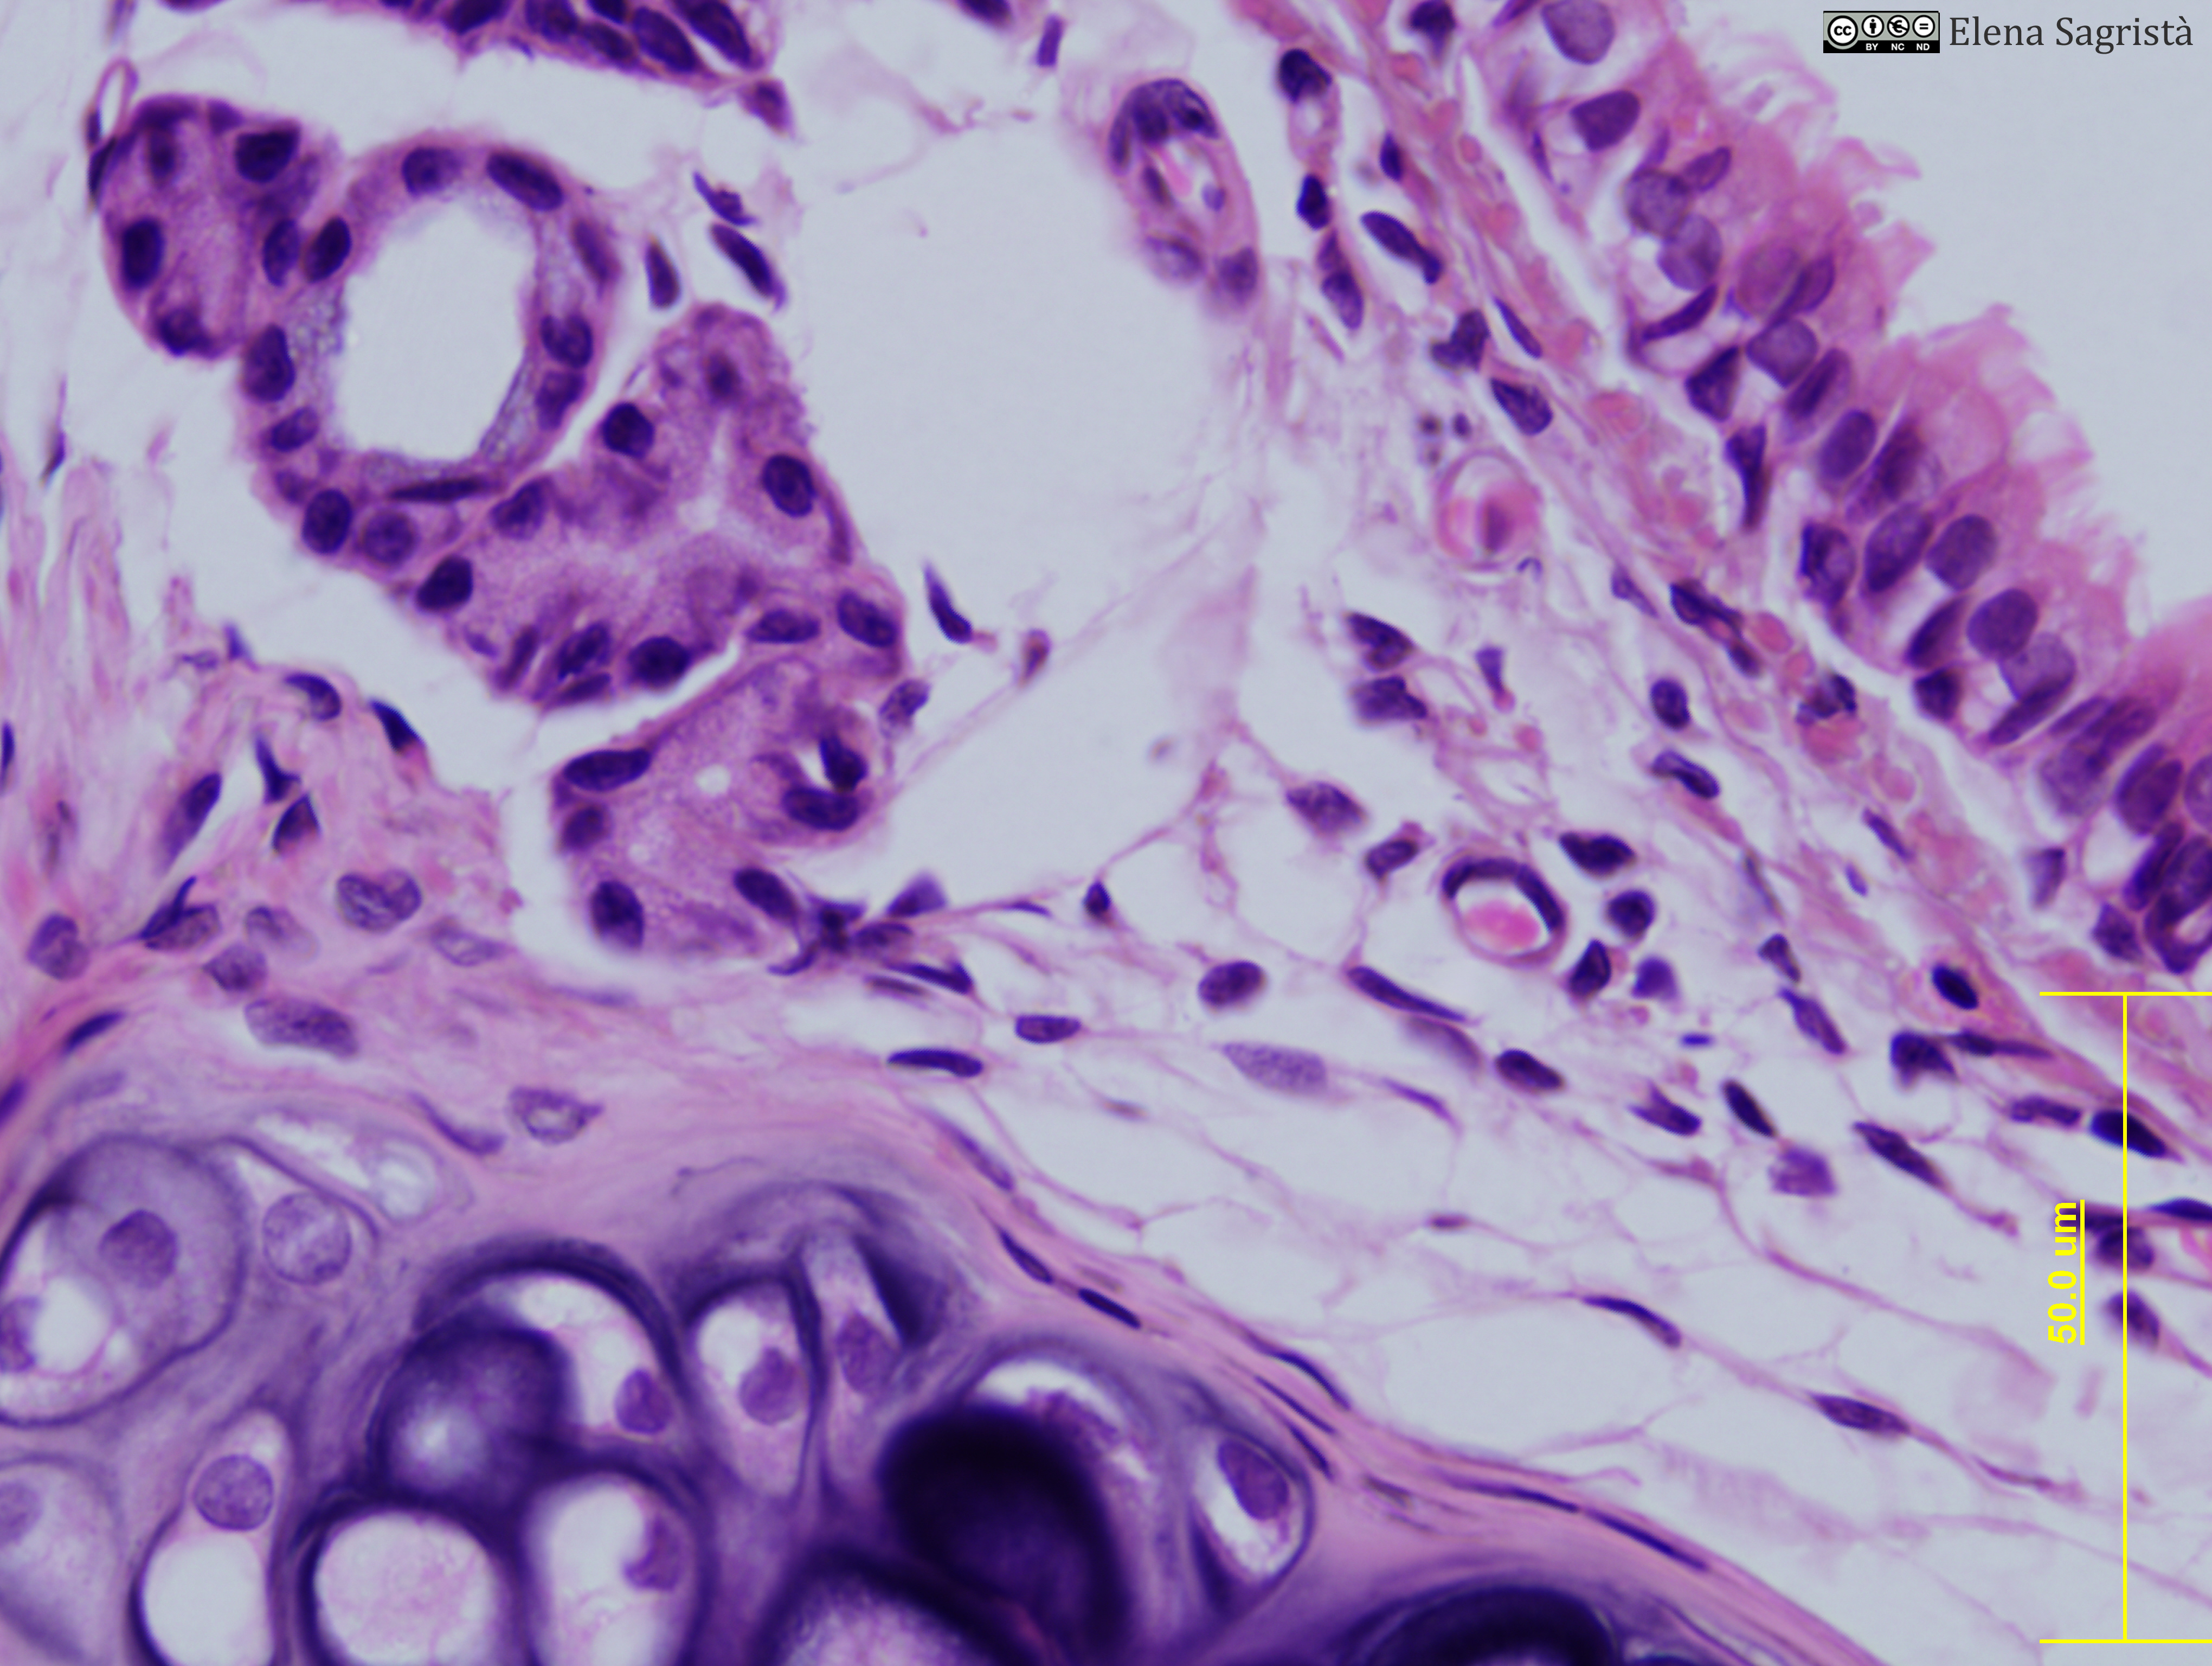

Histologia imatges: 12 Tràquea

Imatges de preparacions histològiques de Tràquea. Microscopia òptica.